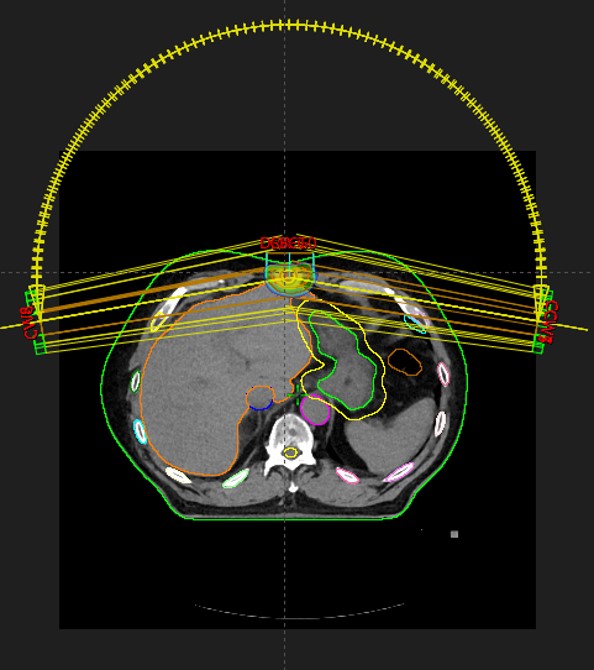

SABR meta pulmonis dex et hepatis, SB Radiochirurgia, 7.5.2022.